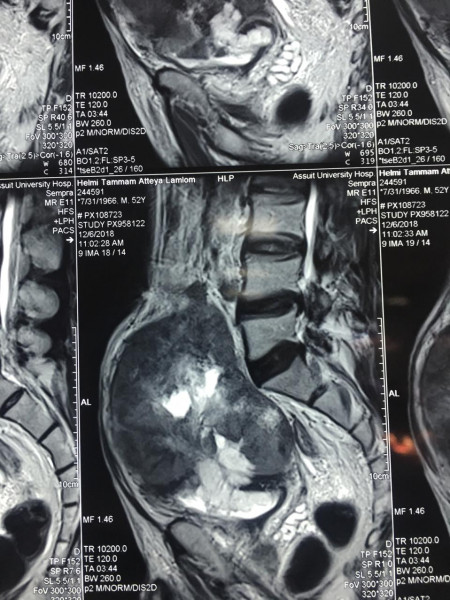

جاء ذلك، بعد إجراء عملية جراحية معقدة لاستئصال الورم لمسن يبلغ من العمر 60 عاماً والتي استغرقت6ساعات متواصلة وذلك بمستشفى جراحة المسالك البولية والكلى الجامعي، تحت رعاية الدكتور طارق الجمال رئيس الجامعة ،والدكتور أحمد المنشاوي عميد كلية الطب ورئيس مجلس إدارة مستشفيات أسيوط الجامعية.

كما كشف الدكتور عمرو أبو فدان المدرس بقسم جراحة المسالك وعضو الفريق الطبي المسئول عن العملية انه فور وصول المريض إلى المستشفى تم خضوعه لعدد من الإشاعات والفحوصات الأولية والتي بينت تضخم حجم الورم مما يستلزم التدخل الجراحي لفصل الورم عن الأنسجة المحيطة وإنقاذ حياه المريض وبالفعل تم إجراء الجراحة بنجاح وخرج المريض من غرفة العمليات دون أي مضاعفات كما تم متابعة الحالة فى غرفة العناية المركزة لمدة 24 ساعة وعند استقرار حالة المريض تم نقله إلى غرفته بمستشفى جراحة المسالك البولية والكلى.